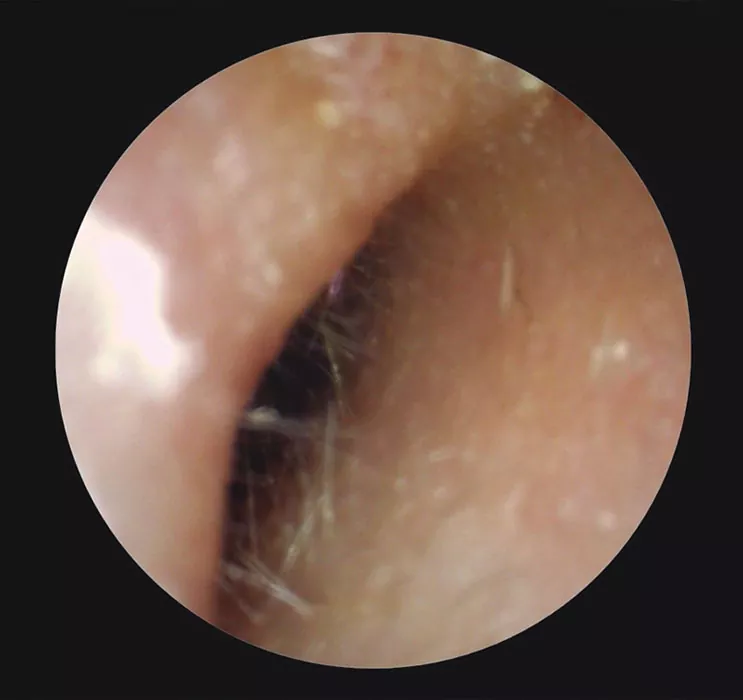

Los traumatismos del oído externo afectan normalmente al PA debido a su posición. El CAE suele lesionarse menos, pero es muy frecuente encontrar heridas en personas con dermatitis (Fig. 4) o en aquellas que suelen usar bastoncillos u otros objetos para limpiar la cera.

Figura 4

Paciente con dermatitis en el CAE del oído derecho. Se observa irritación y herida en pared medial debido a rascado.